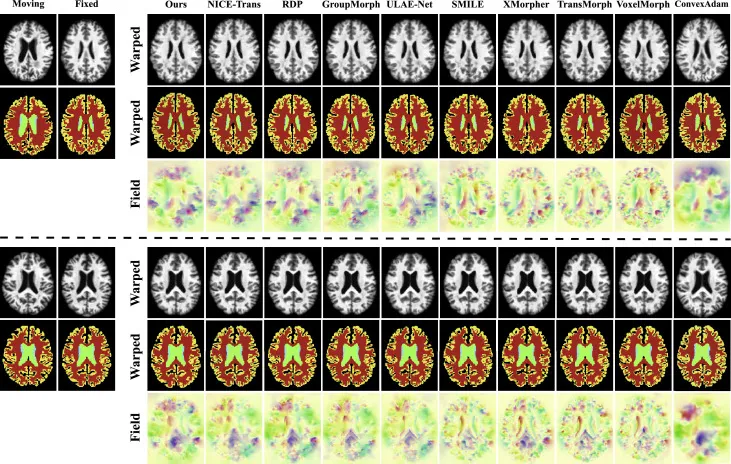

本文在OASIS(脑部T1加权MR)、腹部(CT)和髋关节(CT-MR跨模态)三个具有挑战性的数据集上进行了全面实验。定量结果显示,BIASNet在配准精度方面始终优于现有最先进的方法。在OASIS数据集上,BIASNet的平均DSC达到94.01%,折叠率低至3.83e-2%,显著优于NICE-Trans(93.11%)和RDP(93.06%)。定性结果(图6)和详细分析(图7)进一步验证了其在所有解剖结构上的卓越性能。在腹部数据集上,BIASNet平均DSC为83.41%,折叠率为1.76e-1%,远超第二名RDP(74.61%),显示了其在大形变场景下的强大能力。定性结果(图8)和详细分析(图9)也支持了这一结论。在髋关节数据集的跨模态配准任务中,BIASNet的平均DSC为96.78%,折叠率4.11e-3%,同样优于GroupMorph(95.18%)等方法,定性结果(图10)和详细分析(图11)证实了其优势。

图6. 本方法(Ours)与OASIS数据集中两个病例的其他竞争方法的定性比较。对于每个病例,比较结果按不同方法分为三行。顶部:形变后的移动图像;中部:形变后的移动图像分割标签;底部:每种方法获得的形变场可视化。